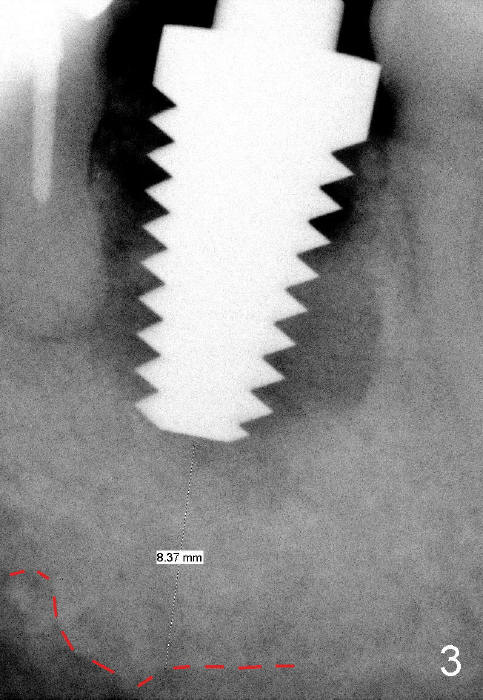

When the tooth is extracted, the socket is extremely large. The largest tapered tap (8x17 mm) basically drops into the socket; it is not stable in the socket (Fig.3). It appears necessary to engage into the nascent bone, which is 8.37 mm long.

Prior to implant placement (Fig.7,9: 7x17 mm with insertion torque 40 Ncm), a mixture of autogenous bone (Fig.8 red particles) and demineralized cortical allograft (white granules) is packed against defective socket walls, particularly apically. It leaves a space in the middle of the socket for implant insertion later on. In this case, the buccal wall around the apex, corresponding to the fistula (Fig.9 >) is severely destroyed, whereas the crestal portion is more or less intact. Three months later, the implant appears yet to osteointegrate (Fig.10), while the fistula disappears (Fig.11). The large implant does not look too overengineered over the alveolus (Fig.12 (lingual view). In fact, the implant has mild mobility. How to fix it?